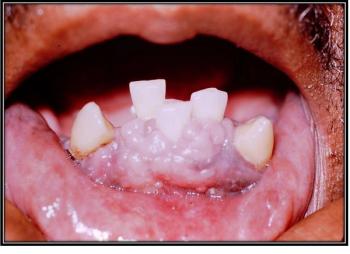

What is in your differential diagnosis for this lesion observed in the mouth of a 52-year-old man?